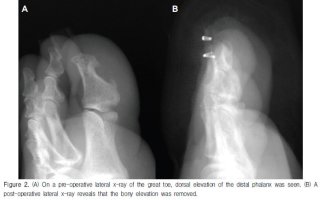

내성발톱 정형외과 발톱이 살을 파고들어 염증 성남내성발톱병원 내성발톱 피부과 내성발톱수술 회복기간 은평구내성발톱병원 내성발톱 자가치료 인천 내성발톱 병원 발톱무좀 길음동내성발톱병원 내성발톱 전문병원 내성발톱 염증치료